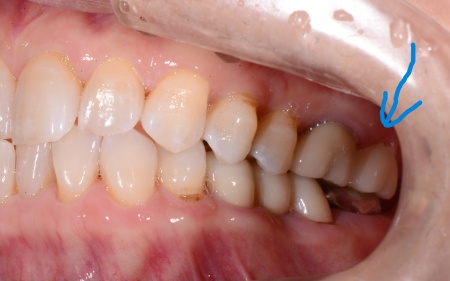

治療後

| 行った治療内容 | 診断内容を丁寧にお伝えしたうえで、抜歯後に歯を補うため、以下2つの治療方法を提案しました。 ①取り外し式の入れ歯 メリット:外科的な処置を行わずに治療でき、比較的短期間で作ることが可能 デメリット:取り外しが必要で、装着したときに違和感を覚えることがある ②あごの骨に人工の歯根を埋め込み、その上に人工の歯を取り付けるインプラント治療 メリット:固定式のためご自身の歯に近い感覚で噛むことができる デメリット:外科手術が必要で自由診療となり、治療期間も比較的長くなる それぞれのメリット・デメリットをお伝えしたところ、患者様は②のインプラント治療を希望されました。併せて治療の流れや外科処置に伴うリスクについてもしっかりとお伝えし、左上奥歯の抜歯とインプラント治療に同意いただきました。 まず、左上の奥歯を抜くと同時にインプラントを埋め込む抜歯即時埋入を行います。 これは、歯を抜いた直後のあごの骨に人工歯根を埋め込む治療方法です。 事前のレントゲン検査で骨の状態を確認し、インプラントを埋め込む位置や角度を慎重に検討したうえで処置しました。 その後、歯ぐきやあごの骨が回復するまで一定期間待ち、インプラントが骨としっかり結合しているかを確認しました。 問題がないことを確認したうえで歯の型取りを行い、インプラントの上に装着する人工歯を作製しています。 最後に完成した人工歯を取り付け、噛み合わせに問題がないかなどを確認し治療を終了しました。 |